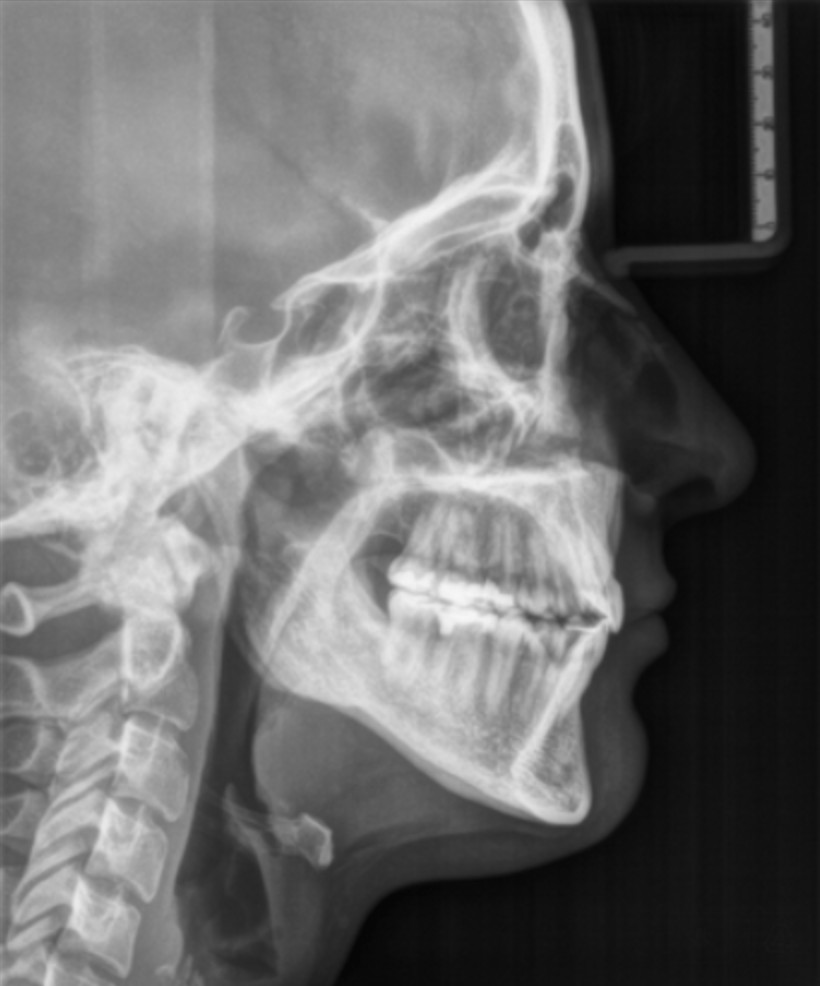

Šoninės galvos skaitmeninės rentgeno nuotraukos (Cefalograma)

Šoninė galvos rentgeno nuotrauka (Cefalograma)

Tai – speciali nuotrauka, naudojama tik ortodontinio gydymo planavimui ir eigai vertinti. Jos dėka gydytojas ortodontas gali atlikti sudėtingus, didelio tikslumo reikalaujančius matavimus ir taip užtikrinti efektyvų gydymą.